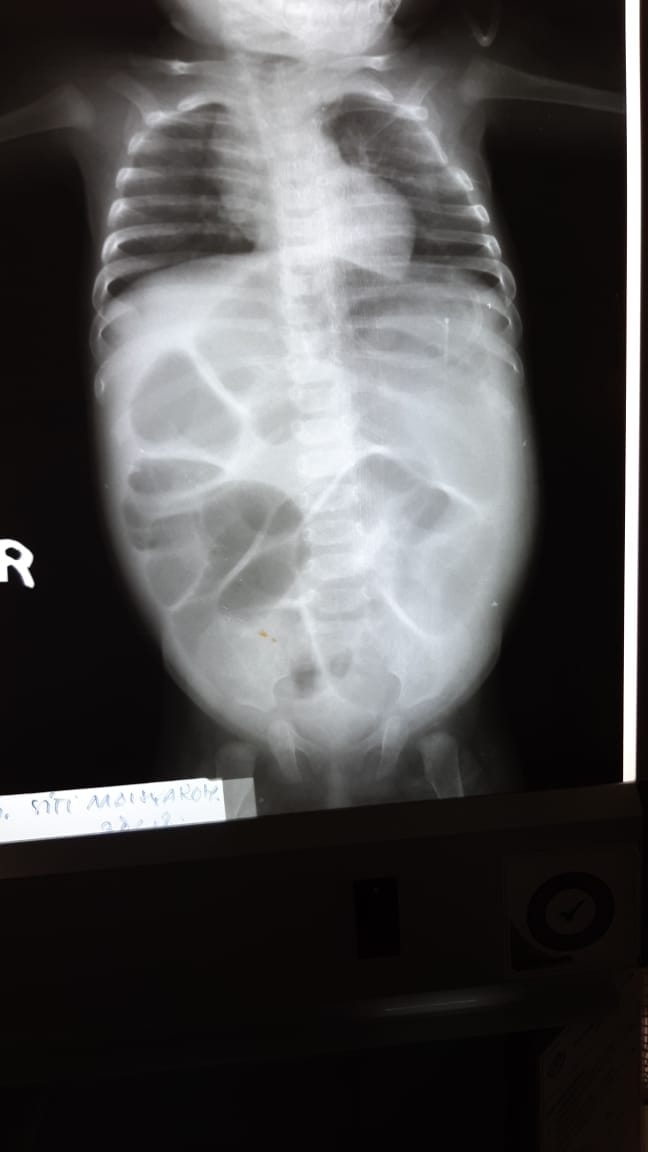

Infant appendicitis with perforation: a case report Fuad Adi Prasetyo; Ekvan Danang Setya; Supangat Supangat

Appendicitis is one of the most common surgical emergencies in children. In the USA, there are 70,000 cases are diagnosed each year. Acute appendicitis is a rare case, barely considered in the diagnoses, and probably causes acute abdominal sepsis in neonates. It affects males generally 75% of the time and 25%-50% of all reported cases occur in premature infant. Almost 50 cases have been reported over the last 30 years. We reported a 5 month-old baby girl whom transferred to our hospital from a peripheral hospital. Previously, the baby diagnosis was low-type obstruction. At the time of admission to our hospital, the baby presented with a history of abdominal distension and did not pass stools after 48 h. Oxygen and oral gastric tube were administered. Exploratory laparotomy surgery was performed through a transverse incision. This report is a retrospective review of one patient with appendicitis perforation presented in our hospital.